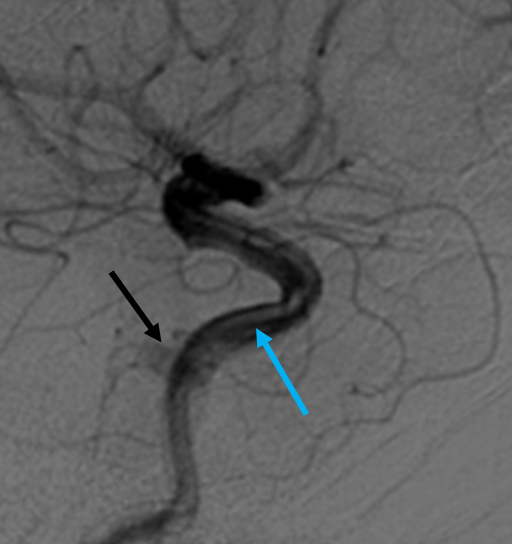

Cerebral angiogram, ICA, lateral projection, shows an incidentally discovered Type B CCF supplied by branches of the MHT with inferior venous drainage via the basilar plexus (cavernous sinus, black arrow; horizontal segment of cavernous ICA, blue arrow). The patient presented with a ruptured brain arteriovenous malformation and was asymptomatic from the CCF. The CCF was observed with follow-up. Image courtesy of John D. Nerva, MD.